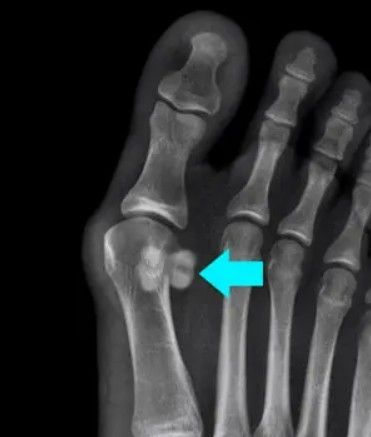

Radiografia (Raio-X):

- É o primeiro exame solicitado.

- Ajuda a identificar fraturas nos sesamoides.

- É essencial para diferenciar entre uma fratura e um sesamoide bipartido (como discutido anteriormente, as bordas são diferentes).

- Pode mostrar sinais de esclerose (endurecimento) óssea, indicando estresse crônico.

Mas, o que é um sesamoide bipartido? É a mesma coisa que uma fratura?

Não, e é fundamental entender a diferença! O sesamoide bipartido é uma condição congênita, ou seja, a pessoa já nasce com ela. Significa que, durante o desenvolvimento, o osso sesamoide não se fundiu completamente, e ele aparece como se estivesse naturalmente dividido em dois (ou mais) pedacinhos.

As principais diferenças são:

- Origem: A fratura é uma lesão adquirida, geralmente por trauma ou sobrecarga. O sesamoide bipartido é uma variação anatômica normal presente desde o nascimento.

- Sintomas: A maioria das pessoas com sesamoide bipartido não sente dor. A dor só aparece se houver uma inflamação (sesamoidite) ou estresse excessivo sobre ele. Já uma fratura causa dor, muitas vezes, intensa.

- Bordas: Em um exame de imagem, as bordas de uma fratura são geralmente irregulares e nítidas. As bordas de um sesamoide bipartido são lisas, arredondadas e bem definidas, indicando que não houve um trauma recente que as tenha quebrado.